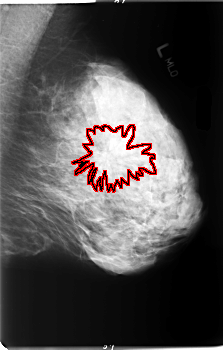

B_3006_1.LEFT_MLO

LEFT_MLO LINES 5936 PIXELS_PER_LINE 3776 BITS_PER_PIXEL 12 RESOLUTION 50 OVERLAY

FILE: B_3006_1.LEFT_MLO.OVERLAY

TOTAL_ABNORMALITIES 1

ABNORMALITY 1

LESION_TYPE CALCIFICATION TYPE PLEOMORPHIC DISTRIBUTION CLUSTERED

LESION_TYPE MASS SHAPE IRREGULAR-ARCHITECTURAL_DISTORTION MARGINS ILL_DEFINED-SPICULATED

ASSESSMENT 5

SUBTLETY 3

PATHOLOGY MALIGNANT

TOTAL_OUTLINES 1

BOUNDARY